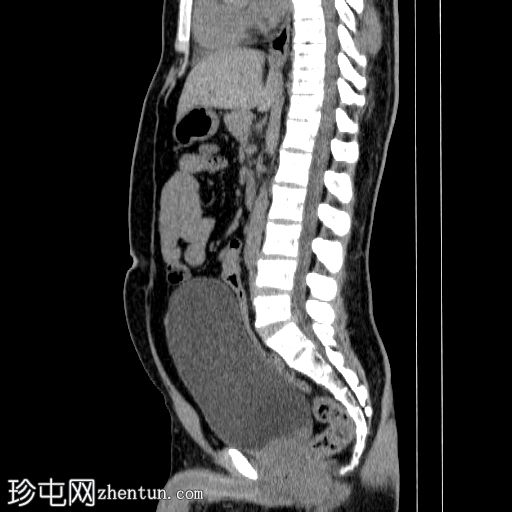

矢状位

平扫

双侧肾结石,无梗阻,较大结石位于左侧肾下盏,最大直径约4 mm,平均CT值约730 HU,伴左侧输尿管轻度扩张。

膀胱明显充盈,高度达脐部,若患者无法排尿,可能需要导尿。